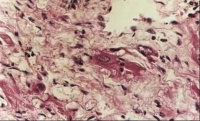

克山病的主要病变是心肌实质的变性、

坏死和纤维化交织在一起心脏呈肌原性普遍扩张,心壁通常不增厚。20%的患者可见附壁血栓及肺、脑、肾、末梢血管的栓塞。光镜可见心肌变性和坏死。心肌变形呈弥漫性,坏死呈灶状分布。病变通常以左心室及室间隔部为重,右心室较轻。点镜主要表现为线粒性肿胀、增生和嵴及肌原纤维破坏。